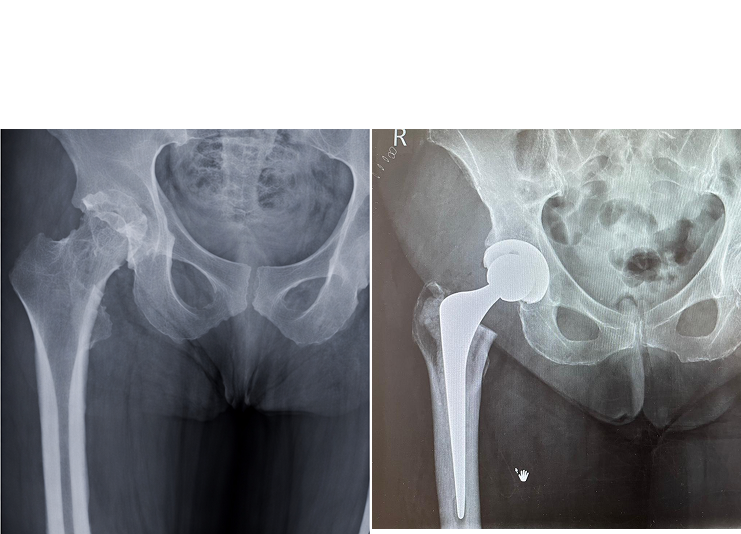

Gallery of Successful Surgeries

Some X-rays from Successful Surgeries